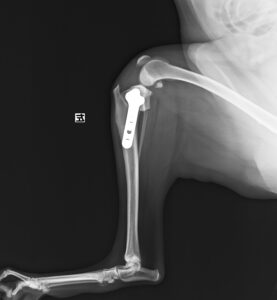

ジャンプした拍子に右後肢跛行とのことでかかりつけ医を受診後、セカンドオピニオンとして当院の整形外科に来院されました。若い雄猫に多く見られる「大腿骨頭すべり症」と診断。ご家族様と相談の上、骨頭切除を実施しました。経過は順調でしたが、その6ヶ月後に逆側も同様に骨折し、同治療を行いました。結果的に両側の骨頭切除が行われましたが、経過は良好です。